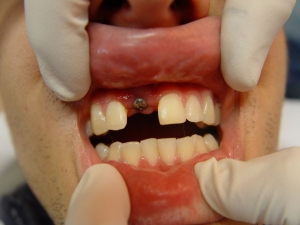

לאחר חצי שנה, חשיפת השתל ובחינת העצם החדשה עם תוצאה רפואית מצוינת

לאחר ריפוי הרקמה הרכה ולקראת שיקום

מבנה מותאם לשתל החדש